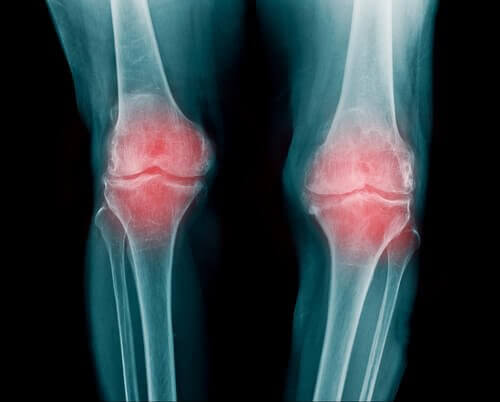

Ревматоїдний артрит

- Ревматоїдний артрит – це запальний процес у суглобах. Насправді це захворювання може вражати суглоби у різних частинах тіла. Найчастіше ознаки ревматоїдного артриту з’являються на пальцях, руках та колінах.

- Найчастіше симптоми ревматоїдного артриту можна помітити на зап’ястках, пальцях та колінах. Втім, це захворювання може вразити й інші частини тіла. Зверніть увагу, що зазвичай артрит асоціюють з розладами у роботі щитоподібної залози та остеоартритом.